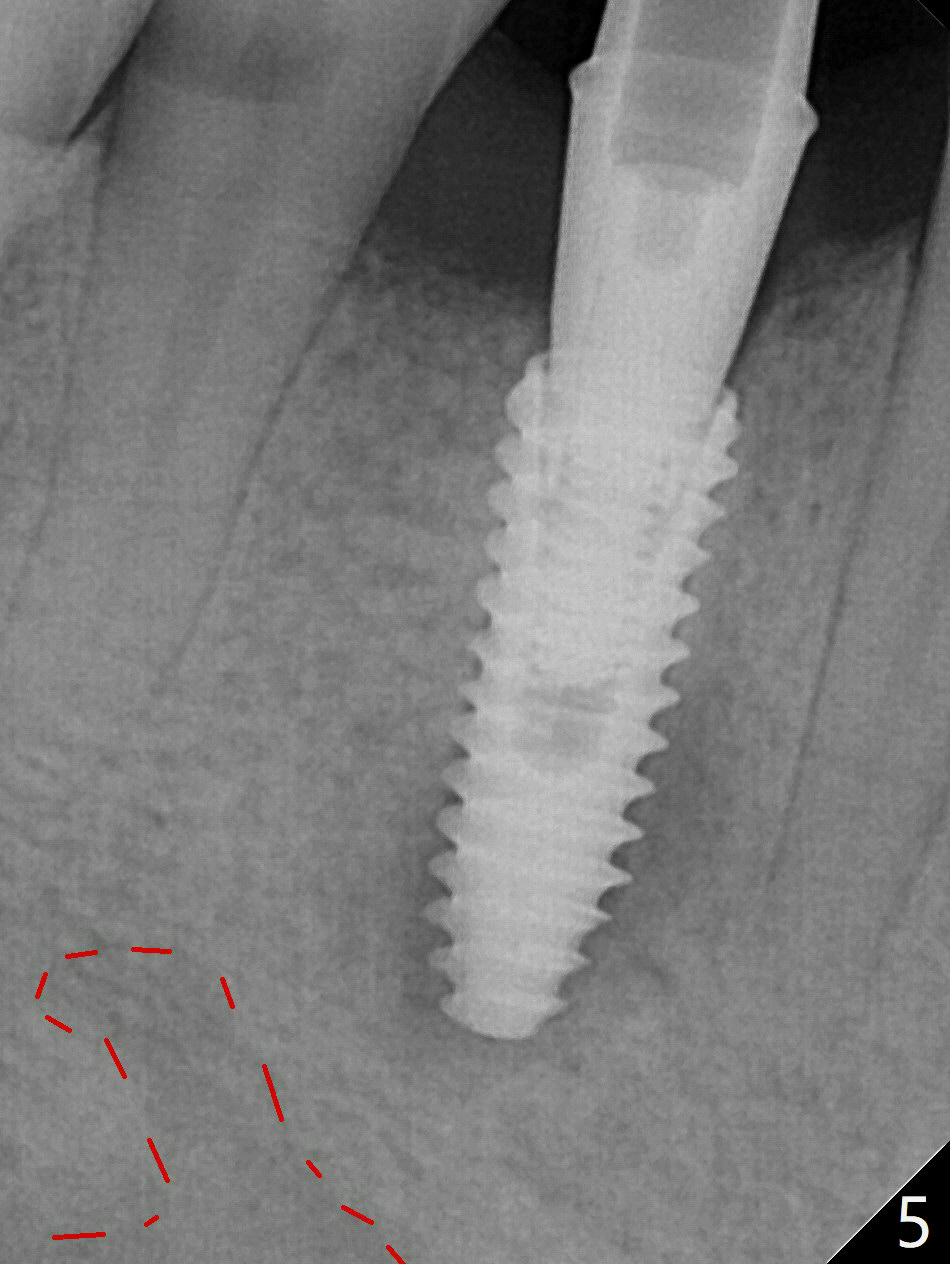

Immediately post extraction and curettage of the large buccal apical lesion, osteotomy is established in the lingual wall of the socket of #28 (slightly distal) for 17 mm vs. 15 mm socket depth (Fig.1 (red line: Mental Loop)). Following sequential osteotomy until 3.5x17 mm drill, a 4x10 mm dummy implant is partially placed with stability (Fig.2,3 (root measurement: mesiodistal 4 mm; buccolingual 7 mm)). A final implant (4x11.5 mm) is placed with insertion torque of 60 Ncm (Fig.4,5). Since the buccal crest is lower with the buccal gingival recession, the implant is intentionally placed deep as well as lingually so that autogenous bone and Vera graft mixture will be placed in the buccal gap (Fig.6 * (gauze at the moment)). The apical lesion decreases 4.5 months postop (Fig.7). Immediate implant and immediate provisional keep the papillae (Fig.8 *), but cannot prevent the buccal plate from atrophy (Fig.9 *). It appears that socket shield is able to accomplish the latter. The bone density next to the coronal threads increases 10 months post cementation (Fig.10 *) and seems to have continued to do so 1 year 4 months post cementation (Fig.11).